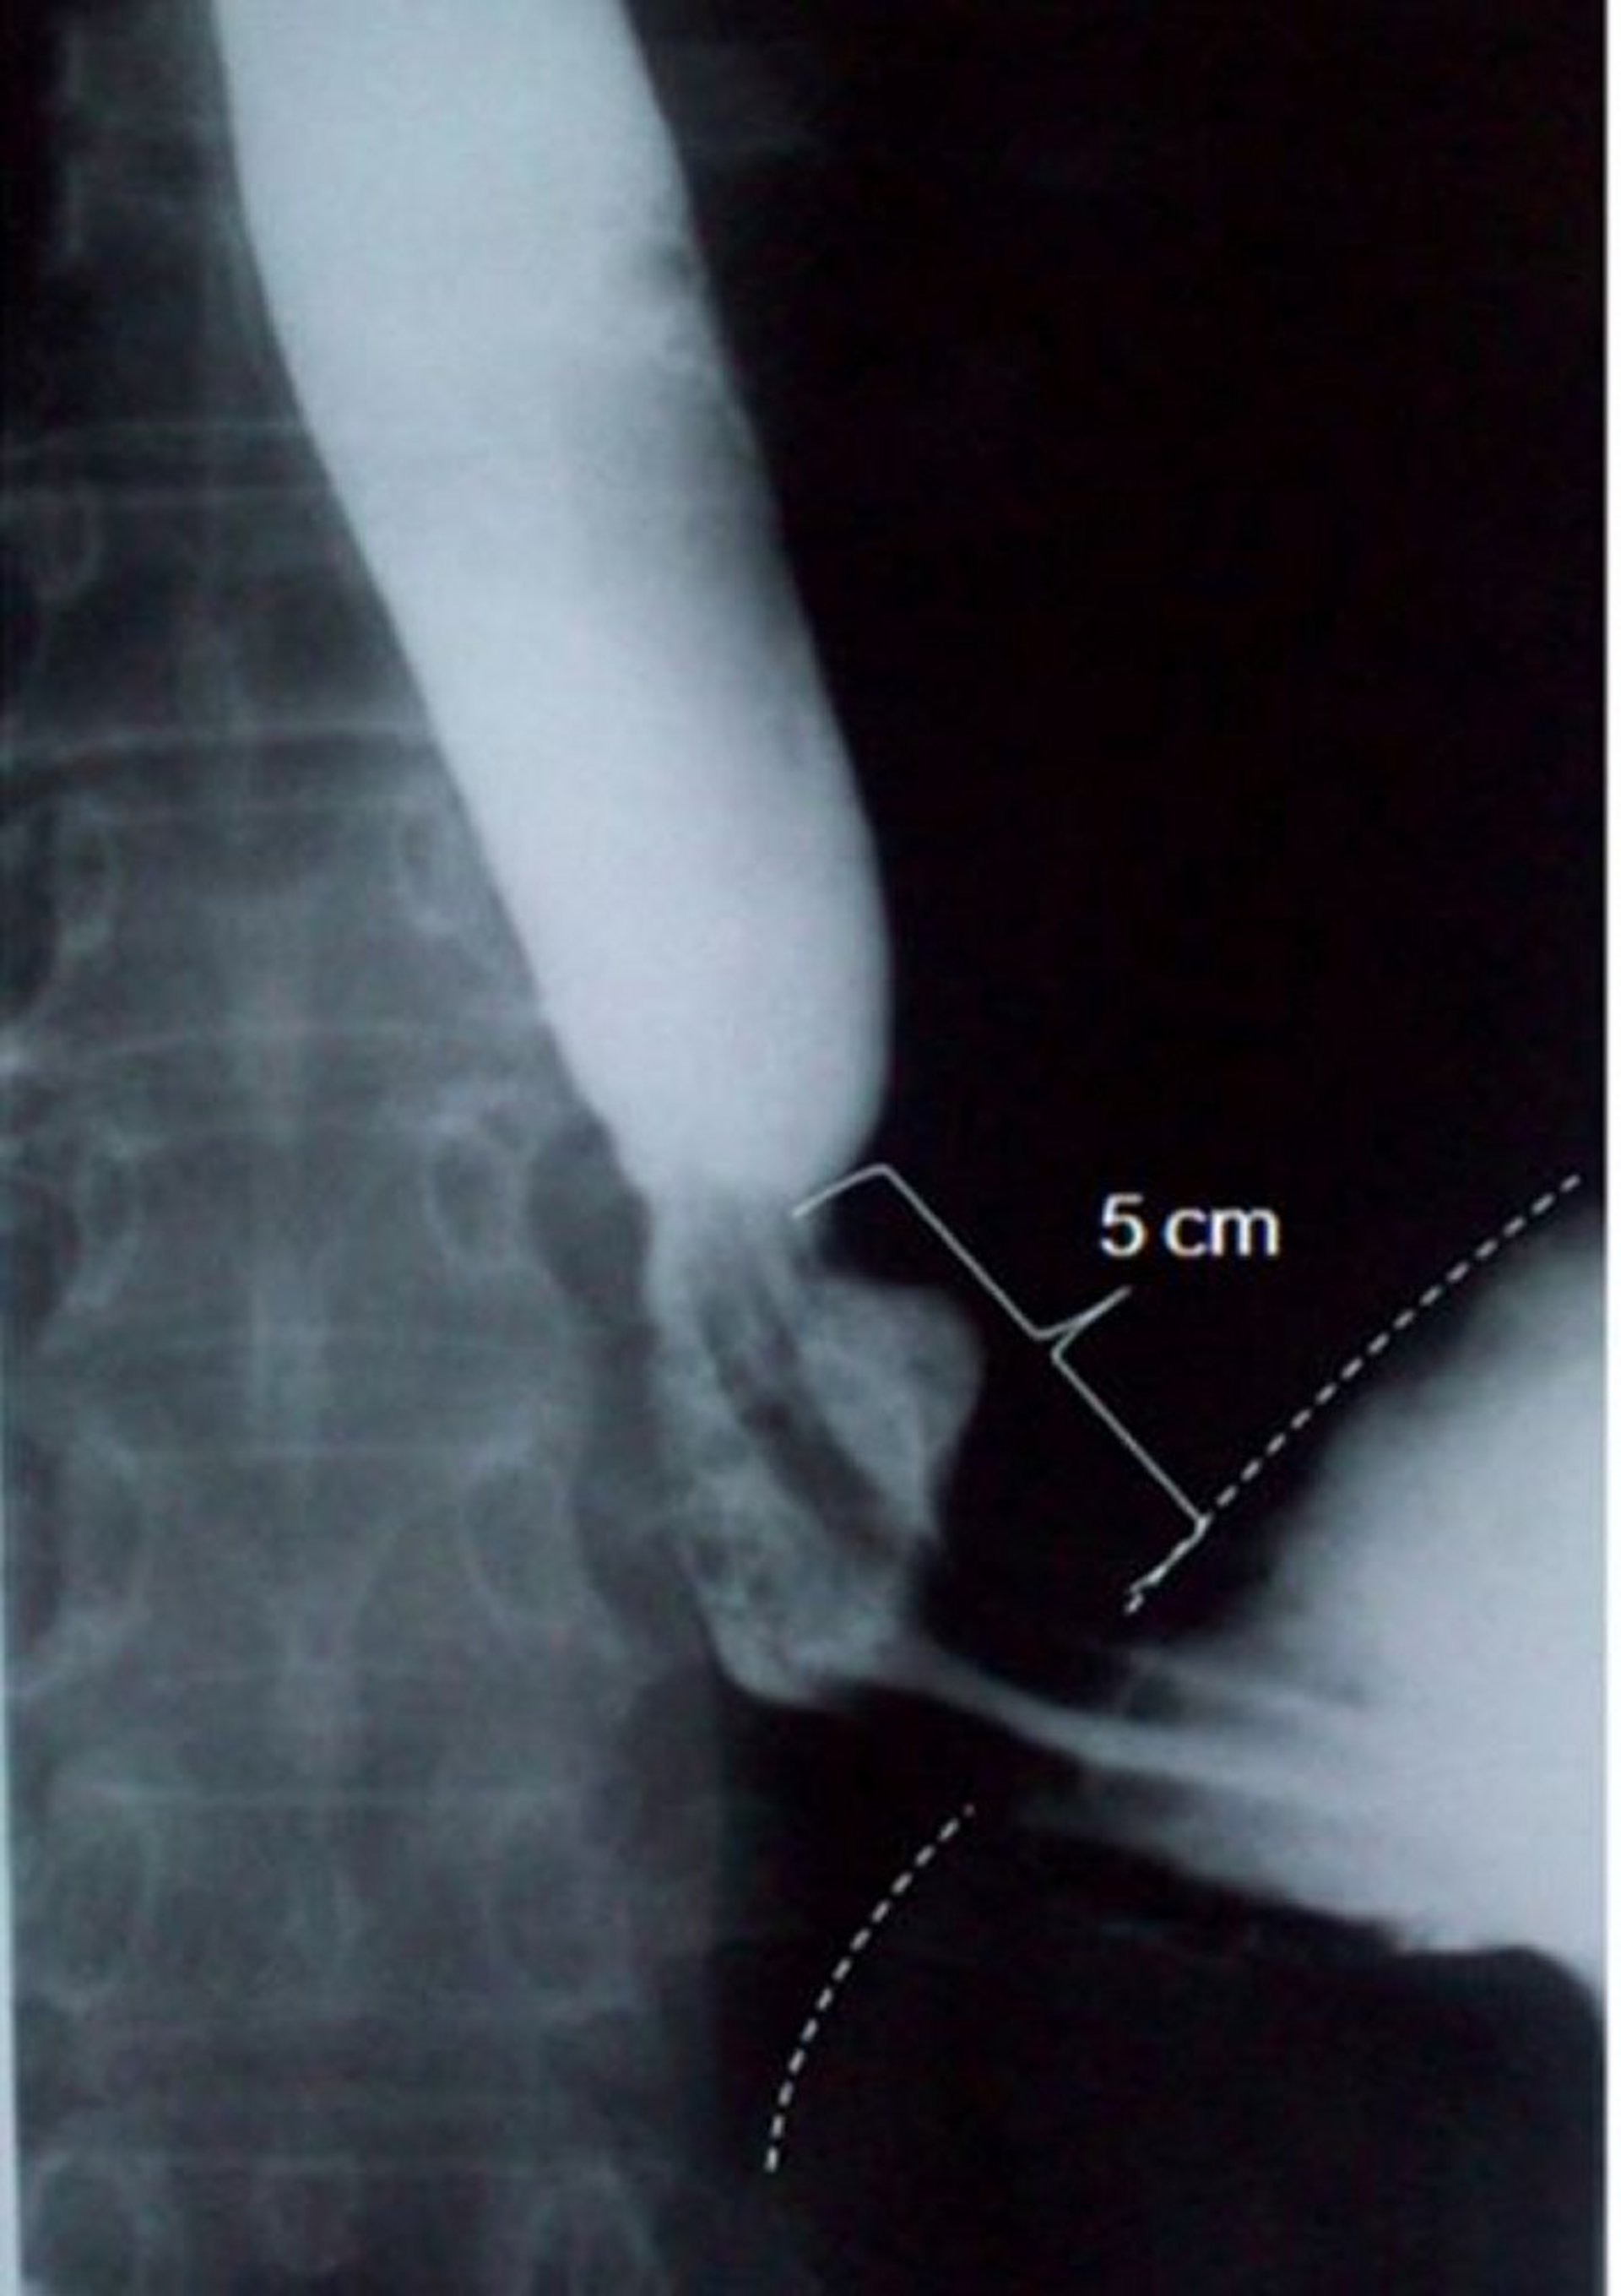

滑脱型食道裂孔ヘルニアを示した食道造影像

この画像には,長軸方向の長さが5cmに及ぶ滑脱型食道裂孔ヘルニアが写っている(破線は横隔膜境界を示している)。